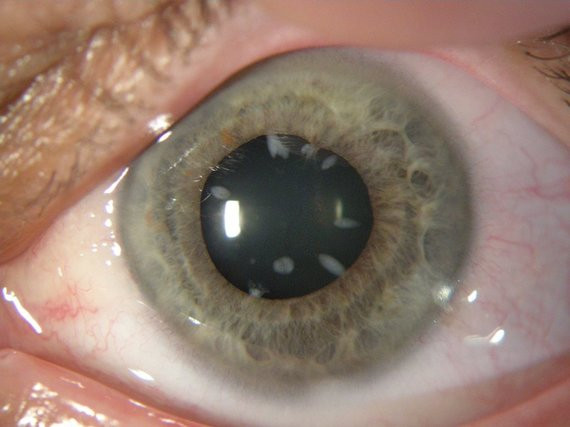

Katarakta – tai akies lęšiuko sudrumstėjimas. Tai – viena dažniausių aklumo priežasčių pasaulyje (46 proc. atvejų, Pasaulinės sveikatos organizacijos duomenimis).

Kataraktų yra įvairių – neretai – labai gražių, akies lęšiukas primena kosmosą ar žvaigždyną. Žinoma, toks vaizdas matomas žvelgiant iš arti į pažeistą akį, o pats pacientas pradeda matyti it „per rūką“. Ir tas „rūkas“ stiprėja.

Iki šiol nėra žinoma, kaip sustabdyti kataratos susiformavimą ar progresavimą. Labai didelė tikimybė, kad kataraktą turėsime visi, tik ne visi spės išsioperuoti. „Vienintelis kelias spręsti šią problemą – operacija. Išoperavus kataraktą ta pačia operacija galima pagydyti ir trumparegystę, ir toliaregystę ar astigmatizmą. Šiandien kataraktos operacijos metu daroma maždaug 1,8-2 mm pjūvis. Lęšis yra nebe kietas, o „minkštas”. Įdėtas į akį jis „išsilanksto“, išsiskleidžia kaip gėlės žiedas. Kataraktos operacija trunka apie 15 minučių, kai kurie medikai spėja ją užbaigti ir per 7 minutes. Žmogus tą pačią dieną išleidžiamas gydytis namuose, gali parvykęs žiūrėti televizorių. Aišku, kurį laiką tenka lašintis priešuždegiminius vaistus.

Kataraktos operacijos galima pasekmė – ragenos endotelio dekompensacija. Dėl šios priežasties ragena pradeda burkti, akį pradeda skaudėti, ženkliai pablogėja matymas. Dėl to gali prireikti daryti ragenos transplantaciją. Laimei, dėl ištobulėjusios technikos tokių operacijų tenka daryti vis mažiau.